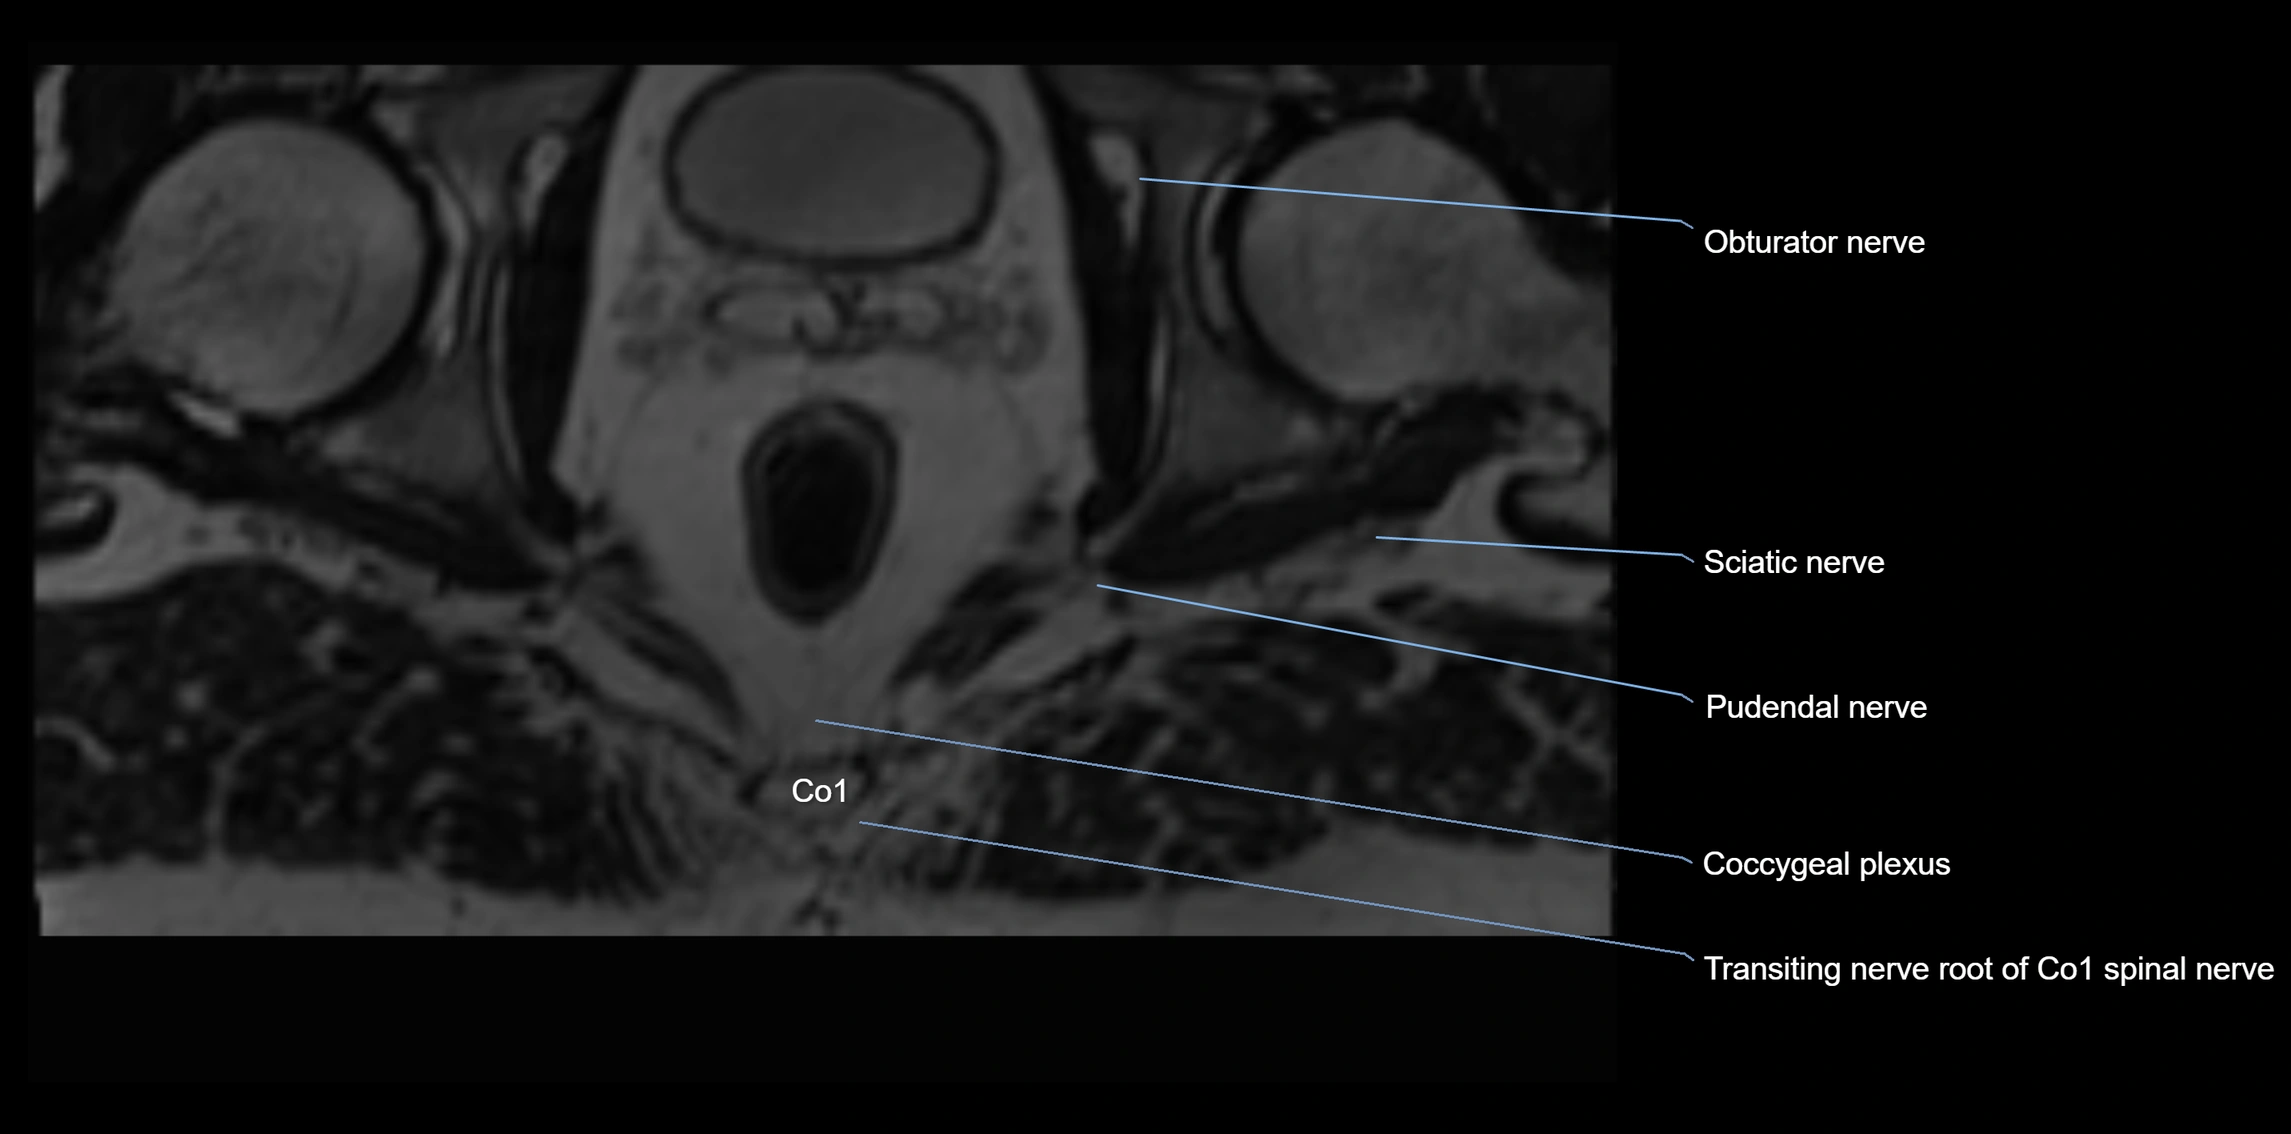

MRI image

image